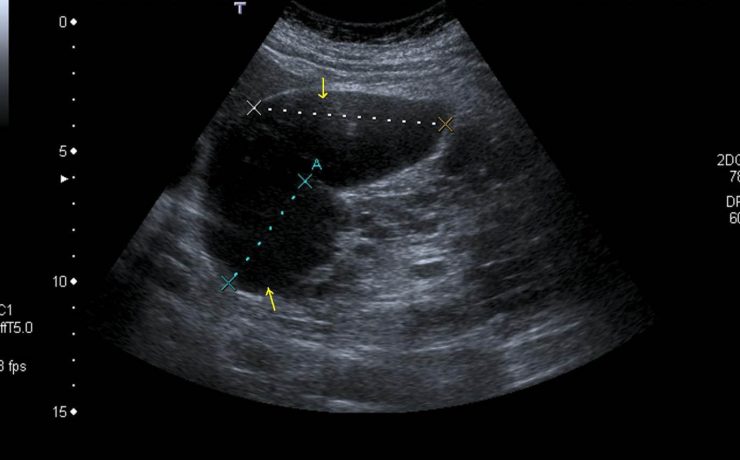

Mastitis granulomatosa idiopática

La mastitis granulomatosa idiopática es un proceso inflamatorio mamario benigno, poco frecuente, de origen desconocido. Se presenta en mujeres en edad reproductiva, entre los 17 y 42 años de edad. El diagnóstico se realiza por exclusión; para ello se utiliza ultrasonido, biopsia por aspiración de aguja fi na o biopsia